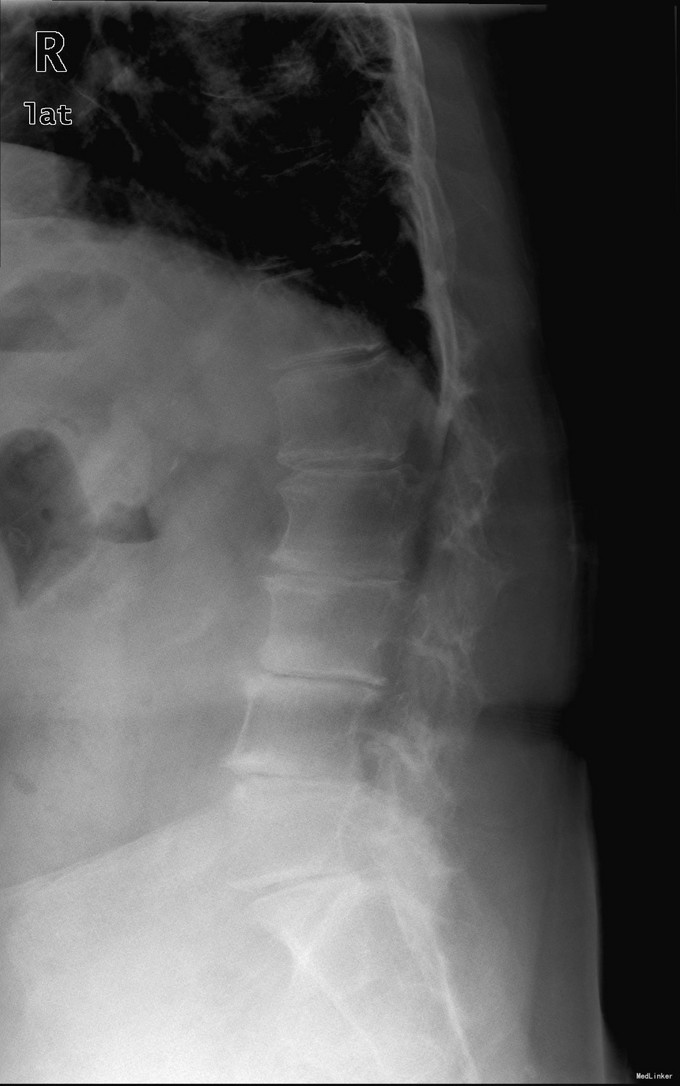

查体:脊柱无明显侧弯,腰背部无压痛,双下肢麻木酸痛,可牵连至脚跟。肌力肌张力可。腰部活动可,前屈后伸时感酸痛,无力。左侧直腿抬高试验阳性。 辅助检查:X线平片:腰椎侧弯前屈,L3椎体轻度滑脱,各椎间隙狭窄,腰椎退行性改变。 MRI:L4-5,L5-S1椎间盘膨出,L2-3,L3-4,L5-S1椎间隙狭窄,S2-3水平骶管内蛛网膜囊肿,腰椎序列不稳定,生理曲度局部后凸。

诊断:1 脊柱侧弯 伴不稳 2椎管狭窄 治疗: 前期微创腰椎侧路融合手术+后期 微创后路经皮内固定